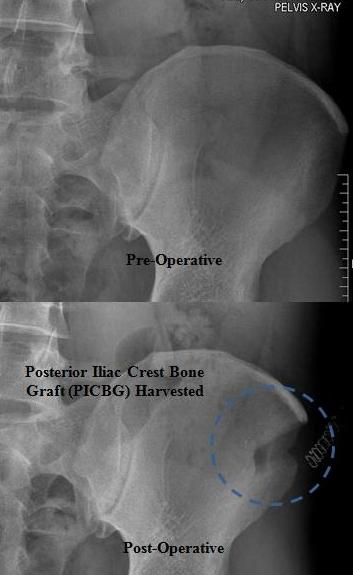

Dento-alveolar surgery (impacted teeth like wisdom teeth and canines, difficult tooth extractions, extractions on medically compromised patients, apicoectomy, bone grafting/bone harvesting or pre-prosthetic surgery) (See Images Below)